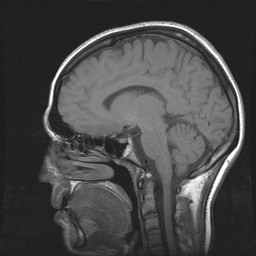

CWZ